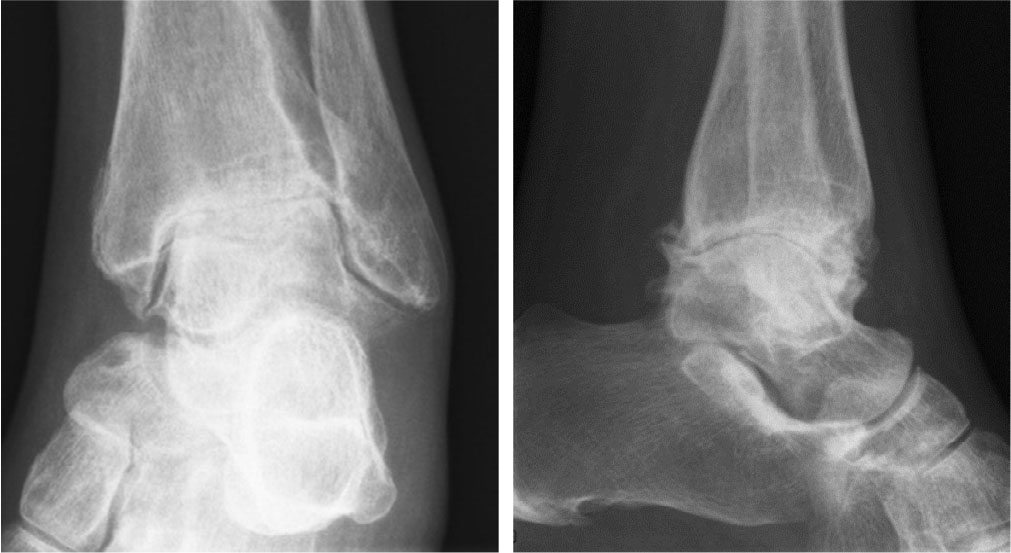

Radiology of Fiona’s ankle in an unloaded image shows cartilage loss from the upper sponge joint (USJ), osteophytes on the ventral and dorsal side of the USJ, and sclerosis (Figure 4). Ankle arthropathy influences movement and load of the forefoot and requires strength and endurance of the stabilising muscles around the ankle, knee and hip, which makes walking exhausting [9]. Although objective evidence of better outcomes is missing, most patients with bleeding disorders are prepared to wear wearing orthopedic shoes and/or insoles. The purpose of custom-made insoles is multiple: comfort, possible correction of a rearfoot deformity, and increasing ankle stability [10]. Based on expert opinion, correction of rearfoot abnormalities is not effective if there has already been bone-on-bone contact.